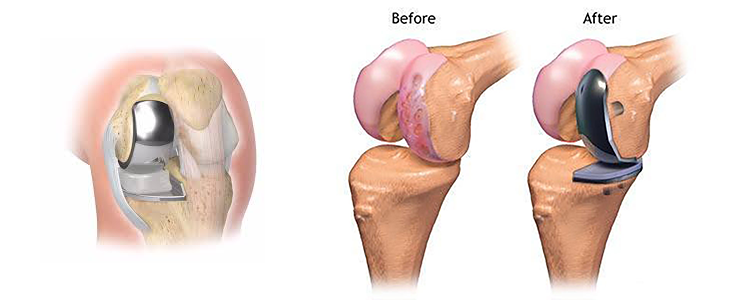

عمل تعویض مفصل زانو نیمه کامل چگونه و به چه روشهایی انجام میشود؟ عمل تعویض مفصل زانو نیمه یا ناکامل چه مزایایی دارد؟ عمل تعویض مفصل زانو جزئی یا ناکامل چه عوارضی دارد؟ روش جراحی جزئی یا ناکامل تعویض مفصل زانو برای مواردی مناسب است که تنها یک قسمت از مفصل زانو آسیب دیده باشد. در این روش بر خلاف جراحی تعویض مفصل زانو کامل که باعث تخریب شدید مفصل زانو میشود، فقط بخش آسیبدیده مفصل با قطعات مصنوعی جایگزین میشود و بخشهای سالم زانو دست نخورده باقی میماند. در این مقاله به بررسی بیشتر این روش جراحی زانو پرداختهایم.

در این جراحی که توسط بهترین دکتر ارتوپد در شرق تهران انجام میشود، بخش آسیبدیده از مفصل زانو با یک پروتز مناسب جایگزین میشود. در این روش، جراح با ایجاد برشی در جلوی زانو، نواحی مختلف زانو را مورد بررسی قرار داده و بخشهای سالم و نواحی را که به جراحی نیاز دارد، به خوبی مشخص میکند. ممکن است پزشک حین جراحی، روش جزئی و ناکامل را مناسب تشخیص نداده و جراحی کامل تعویض مفصل زانو را انجام دهد. پس از جراحی شما باید به طور منظم به پزشک و فیزیوتراپیست خود مراجعه کرده تا میزان بهبودی خود را ارزیابی کرده و هر گونه علائم خود را با پزشک در میان بگذارید.

این روش همچنین با کاهش خطر عوارض همراه بوده و میتواند گزینه مناسبتری برای افراد جوانتر باشد که به دنبال یک راهحل بلند مدت برای درد و ناراحتی زانو خود هستند. تعویض جزئی مفصل زانو میتواند گزینهای مناسب برای بیمارانی باشد که تنها یک بخش از مفصل زانوی آنها آسیب دیده و به دنبال یک روش کمتهاجمی با دوره بهبودی سریعتر هستند. مشاوره با جراح متخصص ارتوپد مانند دکتر مازیار نفیسی میتواند به تعیین بهترین روش جراحی برای هر بیمار کمک کند.